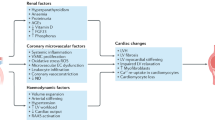

Chronic HF and CKD can be both complicated by the occurrence of cachexia, and interestingly, the underlying pathophysiological mechanisms are similar in the two conditions, as reviewed in the present article. Thus, since chronic heart and kidney interactions are at the base of CRS types 2 and 4, we could propose a new entity called cardio-renal cachexia syndrome (CRCS). It had been previously suggested that common pathogenetic mechanisms underlie body wasting in cachectic states of different chronic heart and kidney diseases [102]. Now we hypothesise that a vicious circle could arise, in which cachexia associated with either HF or CKD may contribute to further damage of the other organ (Fig. 1). Activation of the immune and neuroendocrine systems contribute to the genesis of cachexia, which in turn can negatively affect the heart and kidney function, worsening CRS types 2 and 4. In patients with cardiac cachexia, the same endogenous factors can affect different target organs other than the heart, particularly the kidney. Sustained activation of the immune and neuroendocrine systems and oxidative stress can increase renal vascular resistance and therefore impair renal perfusion, leading to worsening kidney function, i.e. a CRS type 2, or chronic cardio-renal syndrome. Similarly, in renal cachexia, increased levels of pro-inflammatory cytokines can cause progressive left ventricular systolic dysfunction, myocardial cell death, endothelial dysfunction and increased myocardial fibrosis [103], with consequent impairment of the haemodynamic conditions corresponding to the chronic reno-cardiac syndrome, or CRS type 4.